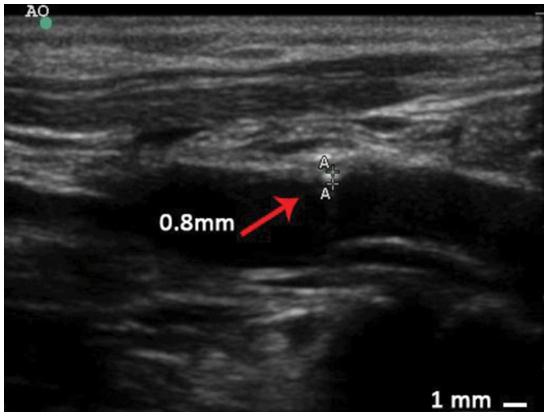

Fig.1 Intima-media thickness measurement of artery walls by ultrasound examination in a rhesus monkey of atherosclerosis (AS). (Zeng, et al., 2015)1, 2

With many years of development of NHP disease models, Creative Biolabs has accumulated much successful experience in NHP disease models and obtained valuable scientific data. Now, to advance the AS research, we provide the well-established and verified AS model in rhesus monkeys, and the related analysis services including but not limited to lipid levels measurement, ultrasound examination (carotid artery, abdominal aorta), immunohistochemistry, histochemical staining, lesion scoring, enzyme-linked immunosorbent assays, and Luminex analysis. If you are interested in our NHP model of AS or have any questions, please feel free to contact us for more information. The professional R&D team of Creative Biolabs will provide you with scientific assistance in your study design and implementation. We are your trusty CRO partner in your preclinical drug development.